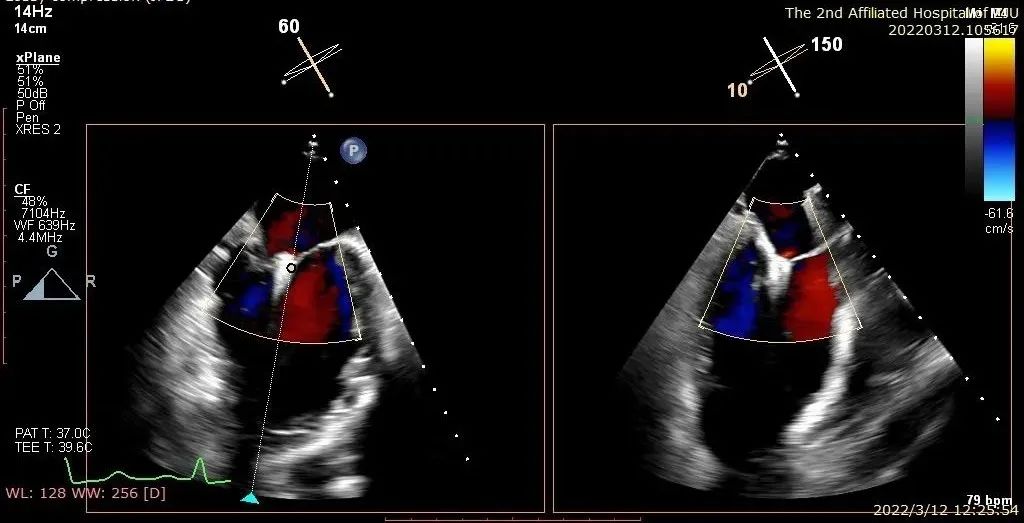

患者一术后二尖瓣零反流